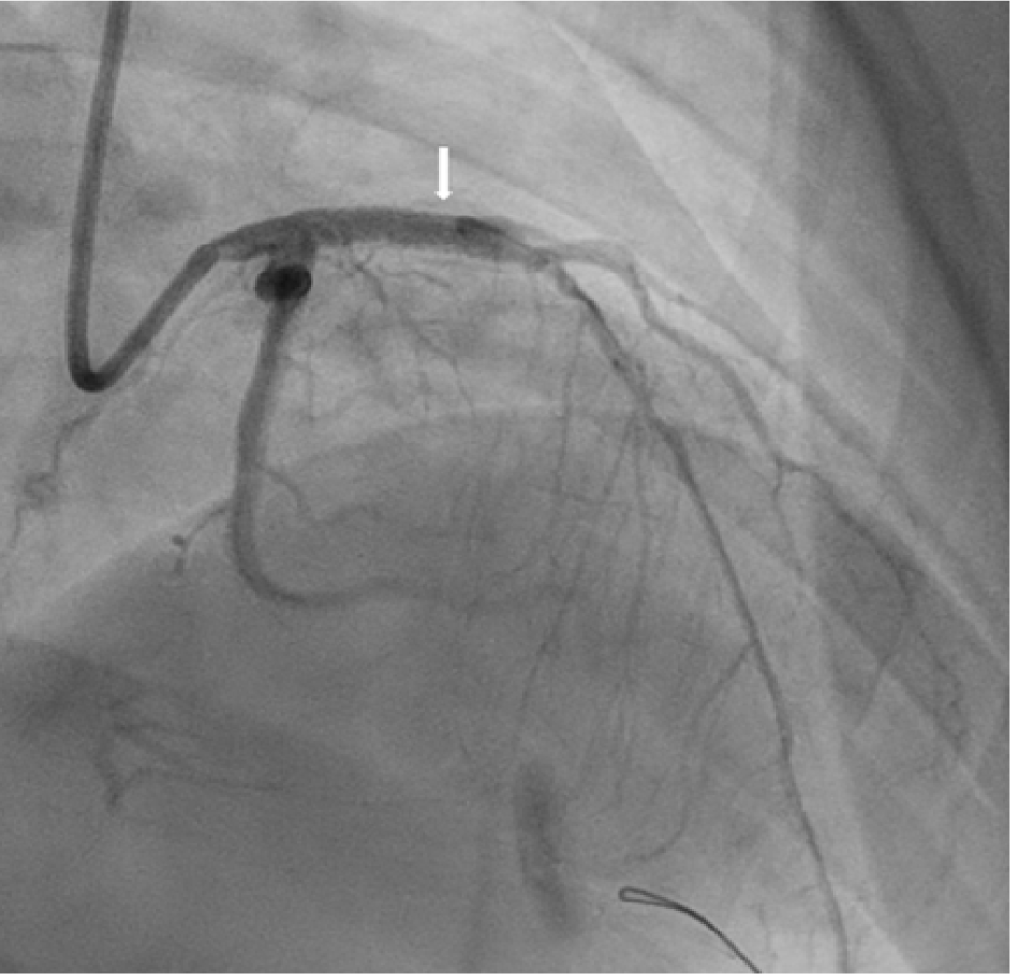

From 1998 to 2023, we performed 13 coronary revascularization procedures in 11 patients at our institution. Demographic and angiographic characteristics of patients with aneurysms are summarized in Table 1. The majority were male (n = 8, 72%), and the median age at KD onset was 3.7 years (range, 1.7–6.0 years). Aneurysms involved various coronary segments, most commonly the RCA and the left anterior descending artery (LAD). Giant aneurysms, defined as ≥ 8 mm in diameter, were identified in 7 of the 11 patients (63%). Most patients received dual antiplatelet therapy or a combination of warfarin and aspirin. Procedural data are summarized in Table 2. The median age at the time of the procedure was 10.1 years (range: 3.9–40.6 years). The treated coronary arteries included the RCA in 9 cases, followed by the LAD in 4 cases, the left circumflex artery in 1 case, and the bypass graft anastomosis site in 1 case. Six patients underwent PTCA, including one case involving stenosis at the anastomosis site of a bypass graft. The median follow-up duration after the PCI was 2.9 years (range, 0.7–13.7 years). All PTCA procedures were immediately successful. Although no neo-aneurysm formation was identified on follow-up imaging, interpretation is limited by the short follow-up duration and the lack of imaging data in a substantial proportion of patients (4 of 11). One patient (17%) developed a dissection post-PTCA. Another patient (17%) experienced restenosis of the RCA six months after initial PTCA, requiring repeat PTCA and DES implantation. The restenosis rate after PTCA (1 of 6, 17%) was comparable to that reported in a previous study (24%) [18]. Four patients underwent DES implantation initially—three following PTCA and one PTCRA. One patient (25%) developed total occlusion of the RCA eight months after stent implantation and underwent successful PTCRA. In total, three patients underwent PTCRA, all with immediate procedural success. Two deaths (18%) were recorded during the follow-up period: one unrelated to coronary artery disease and the other in a patient with severe ventricular dysfunction.